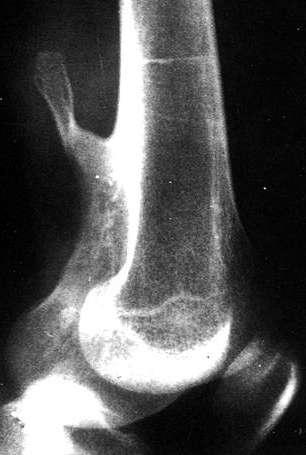

X线表现:① 多数为偏心性骨破坏 (溶骨型)② 局部骨 膨胀性,骨皮质变薄形成薄层骨壳,无硬化边③ 大小不一的分隔小房呈肥皂泡状, 并见骨嵴。

④ 无骨膜反应,⑤一般不穿破关节软骨

桡骨远端偏侧性膨胀性骨质破坏,中有骨嵴。

骨巨细胞瘤(GCT)

临床与病理:1、年龄:20-40岁,约65%;2、部位:长管状骨骨端,膝关节附近居多